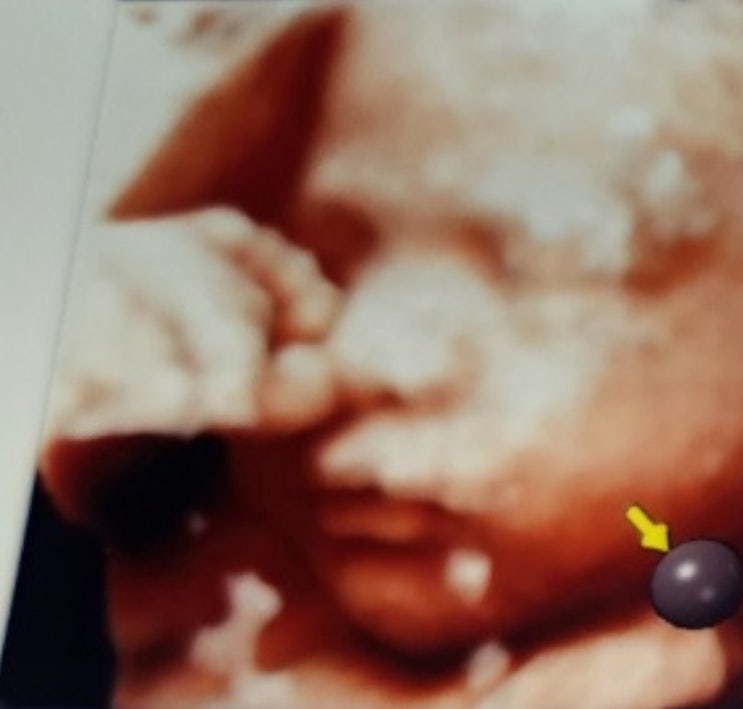

240110 첫 임신일기 :: 3차초음파 찍기, 내가 입원이라니! 코니뉴본박스 신청하기

임신 알게된지 엊그제 같은데 벌써 꽉찬 8개월을 향해 달려가는듕ㅎ 미루고 미루다가 드디어 #초음파앨범 ...